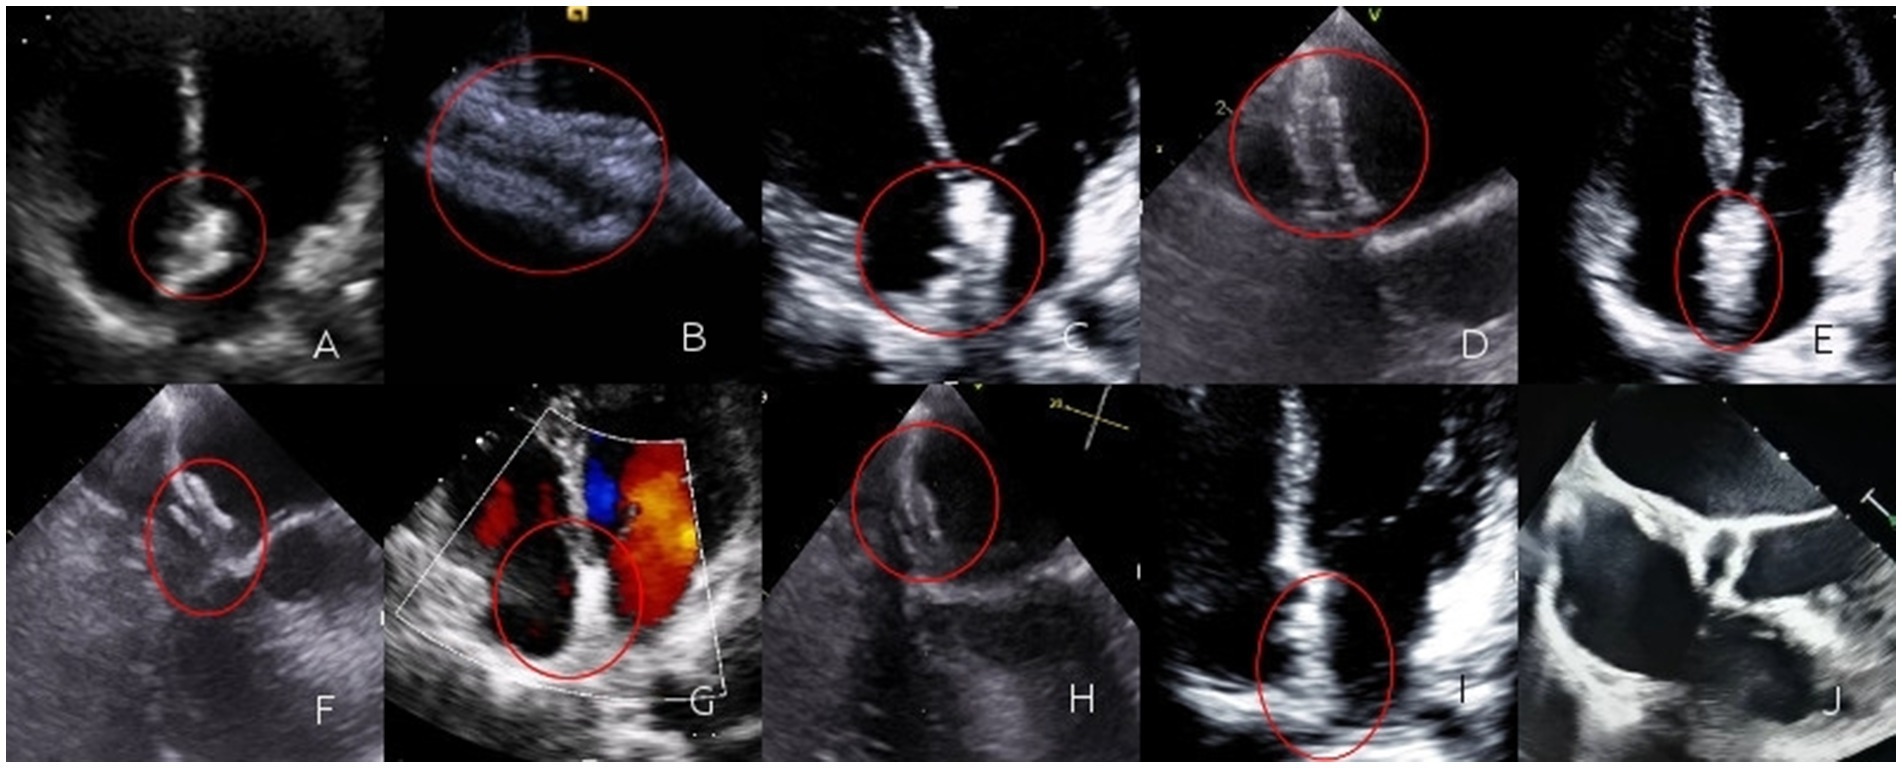

During the 1-month follow-up, 52 patients in the biodegradable occluder group rechecked cTTE. Among them, 8 patients had a grade I shunt, 4 patients had a grade II shunt, and no obvious shunt was observed in the rest. In the metallic occluder group, 70 patients rechecked cTTE. Among them, 13 patients had a grade I shunt, 8 patients had a grade II shunt, and no obvious shunt was observed in the rest. Rates of residual shunt were similar between two groups (7.7% vs. 11.4%; p = 0.493). During the 6-month follow-up, 45 patients in the biodegradable occluder group rechecked cTTE. Among them, 8 patients had a grade I shunt, 3 patients had a grade II shunt, and no obvious shunt was observed in the rest. In the metallic occluder group, 63 patients rechecked cTTE. Among them, 10 patients had a grade I shunt, 7 patients had a grade II shunt, and no obvious shunt was observed in the rest. Rates of residual shunt were similar between two groups (6.7% vs. 11.1%; p = 0.432). During the 1-year follow-up period, 38 patients in the biodegradable occluder group had a recheck cTTE. Among them, 7 patients had a grade I shunt, 1 patient had a grade II shunt, and no obvious shunt was observed in the rest. In the metallic occluder group, 51 patients rechecked cTTE. Among them, 8 patients had a grade I shunt, 4 patients had a grade II shunt, and no obvious shunt was observed in the rest (Figure 2). Rates of residual shunt were similar between two groups (3.6% vs. 7.8%; p = 0.291).

Figure 2. (A) Immediately after the operation, TTE revealed three layers of interlayers in the contour of the occluder. The occluder was highlighted and moved synchronously with the atrial septum; (B) Immediately after the operation, a circular contour of the left disc could be seen by TEE; (C) One month after the operation, TTE revealed three layers of interlayers in the contour of the occluder. The occluder was highlighted and moved synchronously with the atrial septum; (D) One month after the operation, a circular contour of the left disc could be seen by TEE; (E) Three months after the operation, TTE revealed three layers of interlayers in the contour of the occluder. The occluder was highlighted and moved synchronously with the atrial septum; (F) Three months after the operation, a circular contour of the left disc could be seen by TEE; (G) Six months after the operation, TTE revealed the occlude was highlighted, the contour of the occluder was blurred, the three-layer dissection structure gradually became blurred, and it moved synchronously with the atrial septum; (H) Six months after the operation, a circular contour of the left disc could be seen by TEE, the occluder gradually degrades; (I) One year after the operation, the TTE was not clear enough, and the three layers of interlayers could not be observed; (J) One year after the operation, TEE revealed regenerated tissue in the form of the occluder. The regenerated tissue faintly formed a three-layer interlayer with the atrial septum.